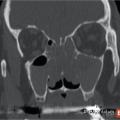

Rhinosinusites de l’enfant

La rhinosinusite se définit comme une inflammation de la muqueuse d’un ou plusieurs sinus de la face. Chez l’enfant, le terme de rhinosinusite remplace celui de sinusite car il est exceptionnel que l’atteinte de la muqueuse sinusienne soit isolée comme dans les sinusites dentaires ou précède l’atteinte du nez comme dans les…